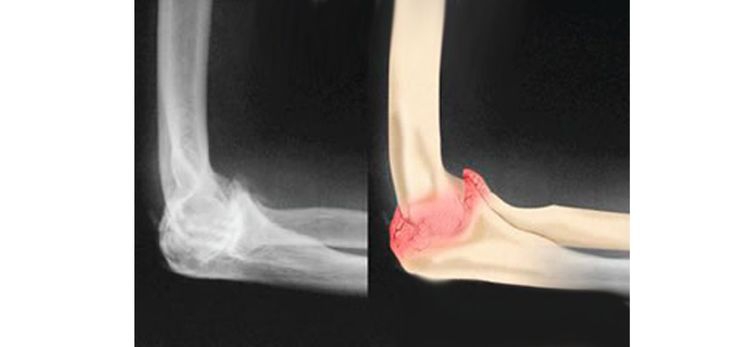

5.肱骨外髁骨折

对于一些移位不重的肱骨外髁骨折,肘关节镜下可以进行骨折的复位及内固定,由于损伤小,病人更容易接受。